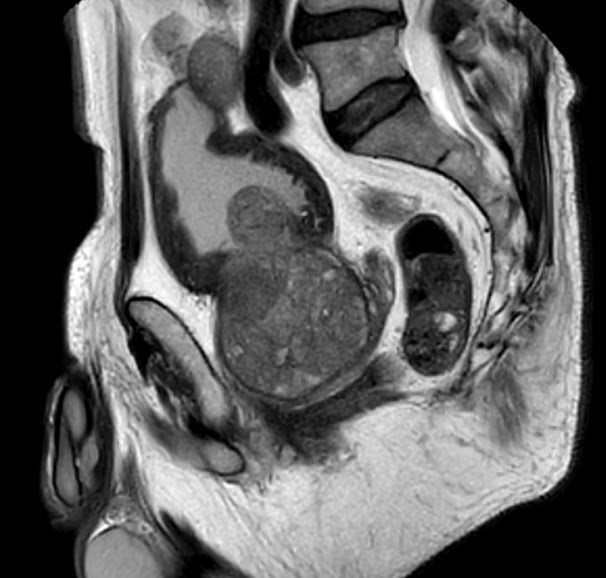

L’IRM de la prostate, et plus spécifiquement l’IRM multiparamétrique, est désormais considérée comme le meilleur examen d’imagerie pour détecter le cancer localisé de la prostate. Elle permet non seulement de visualiser l’extension locale d’une tumeur, mais elle aide aussi à identifier d’éventuelles atteintes de la capsule prostatique, des vésicules séminales ou des ganglions pelviens. Malgré les avantages de l’IRM, l’accès à ces examens peut être limité dans certaines régions en raison d’un manque de machines adéquates. De plus, la réalisation d’une IRM informée nécessite une technique spécialisée que tous les centres d’IRM ne maîtrisent pas encore.

• Visualisation des Zones Suspectes : L’IRM aide à identifier des zones à forte suspicion de cancer, différenciant ainsi les cancers à faible risque des formes plus agressives.